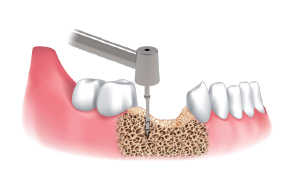

Fresa punta para marcar sitio de obtención y de implante.

Seleccionar fresa Ø3.5/4.0 e insertar el stopper en la fresa seleccionada. Luego poner la pantalla en el stopper Ø3.5&4.0.

Fresar entre 300 a 500 RPM con irrigación y obtener las limallas de hueso.